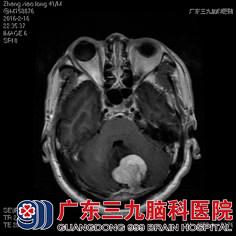

张先生发病以来神志清楚,查体结果显示:神经系统查体未见明显异常,头颅磁共振提示“左侧小脑占位性病变”。完善了所有术前检查及准备,神经外六科的金鑫医生为其实施了左侧小脑半球肿瘤切除术,手术过程顺利,病理结果回报:血管周细胞瘤。

术前CT及核磁共振